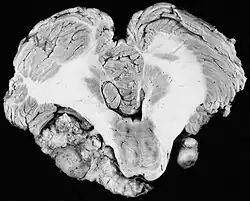

In 1777, Eduard Sandifort of Leiden, the Netherlands, wrote a postmortem first description of a vestibular schwannoma. He observed "a certain hard body adherent to the auditory nerve," and concluded this cause of deafness was beyond the reach of medication or surgery and was therefore incurable. The Schwann cells that multiply to form a VS on the vestibulocochlear nerve were identified 60 years later in 1838 by the German physiologist Theodor Schwann. In 1895, Thomas Annandale, a general surgeon at the Royal Infirmary in Edinburgh, Scotland, was the first to successfully localize and surgically remove a VS.[43] Finger dissection of VS to 'shell out' the tumor was typical. The main goal when dealing with large tumors was preservation of life.

Early operations

In the early 1900s the mortality rate for VS surgery was in the range of 75 to 85%. Surgeons typically delayed invasive intervention as long as possible as a last resort. Harvey Cushing (1869–1939) is known as 'the father of neurosurgery for VS.' His basic study published in 1917 was entitled Tumors of the Nervus Acusticus and the Syndrome of the Cerebellopontine Angle. Cushing perfected the retrosigmoid surgical approach, and by doing suboccipital craniotomy and subtotal removals he was able to reduce mortality to 4% by 1931. Cushing worked at Brigham Hospital in Boston. An equally famous specialist for VS at Johns Hopkins in Baltimore was Walter E. Dandy (1886–1946), a former pupil of Cushing who advocated total tumor removals. In 1931, he reported a complete removal with preservation of the facial nerve.